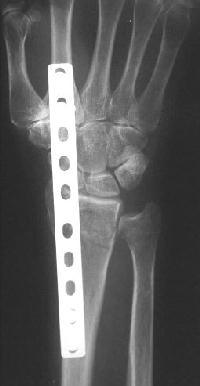

Clinical Example: Distraction plate fixation distal radius fracture

distal radius fracture